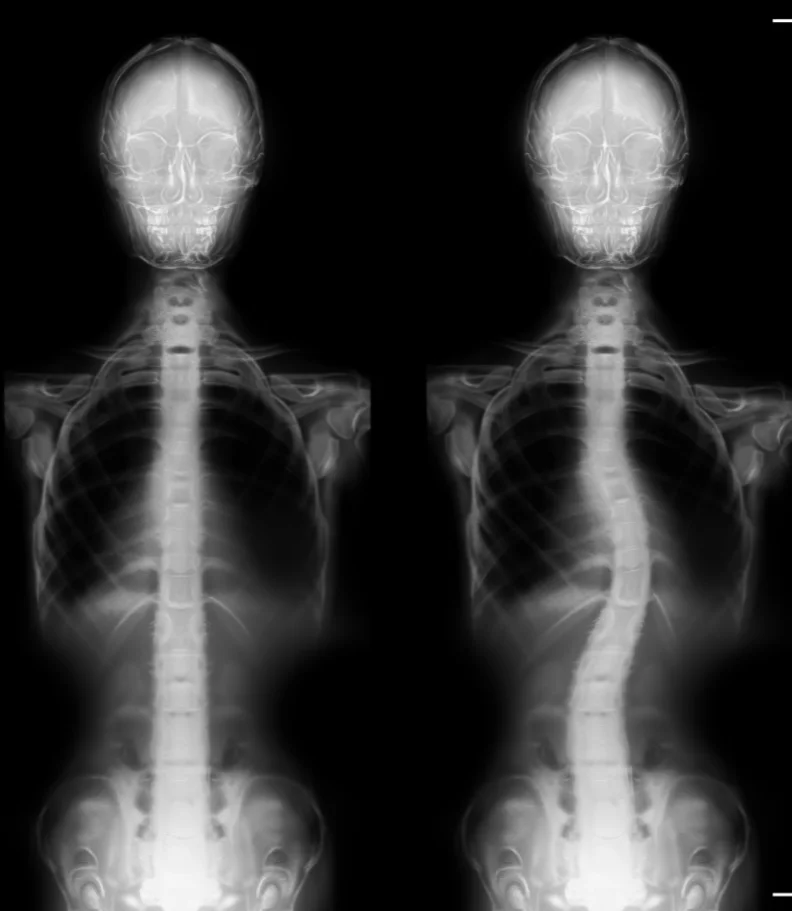

Are you suffering from scoliosis in Greenville SC? In most cases, scoliosis comes from a curve in the spine that slowly gets worse as time passes. For an individual to have scoliosis they must have at least a 10-degree curve in the spine but in many cases, the angle is greater. Scoliosis is usually accompanied by a lot of pain. But you're in luck! With a proactive treatment plan, chiropractors in Greenville SC are able to treat and prevent scoliosis.

Despite a lot of research as to why scoliosis happens, there is no exact one reason. Researchers do claim that it is more common in young women. Most of the time scoliosis stems from one vertebra being in the incorrect place. An imbalance is created as the spine muscles start to favor certain parts of the back. These imbalances and misalignments cause the spine to start to curve. Many teachers are able to spot scoliosis in their students due to the amount of time spent with them and the obvious tilt of a student with scoliosis. Unlike other spinal conditions, scoliosis can not be fixed by simply fixing your posture.

A simple x-ray can be performed by your healthcare professional in order to determine what the best method of treatment should be. Here at GreenLife Wellness in Greenville SC we are educated and experienced in diagnosing scoliosis.